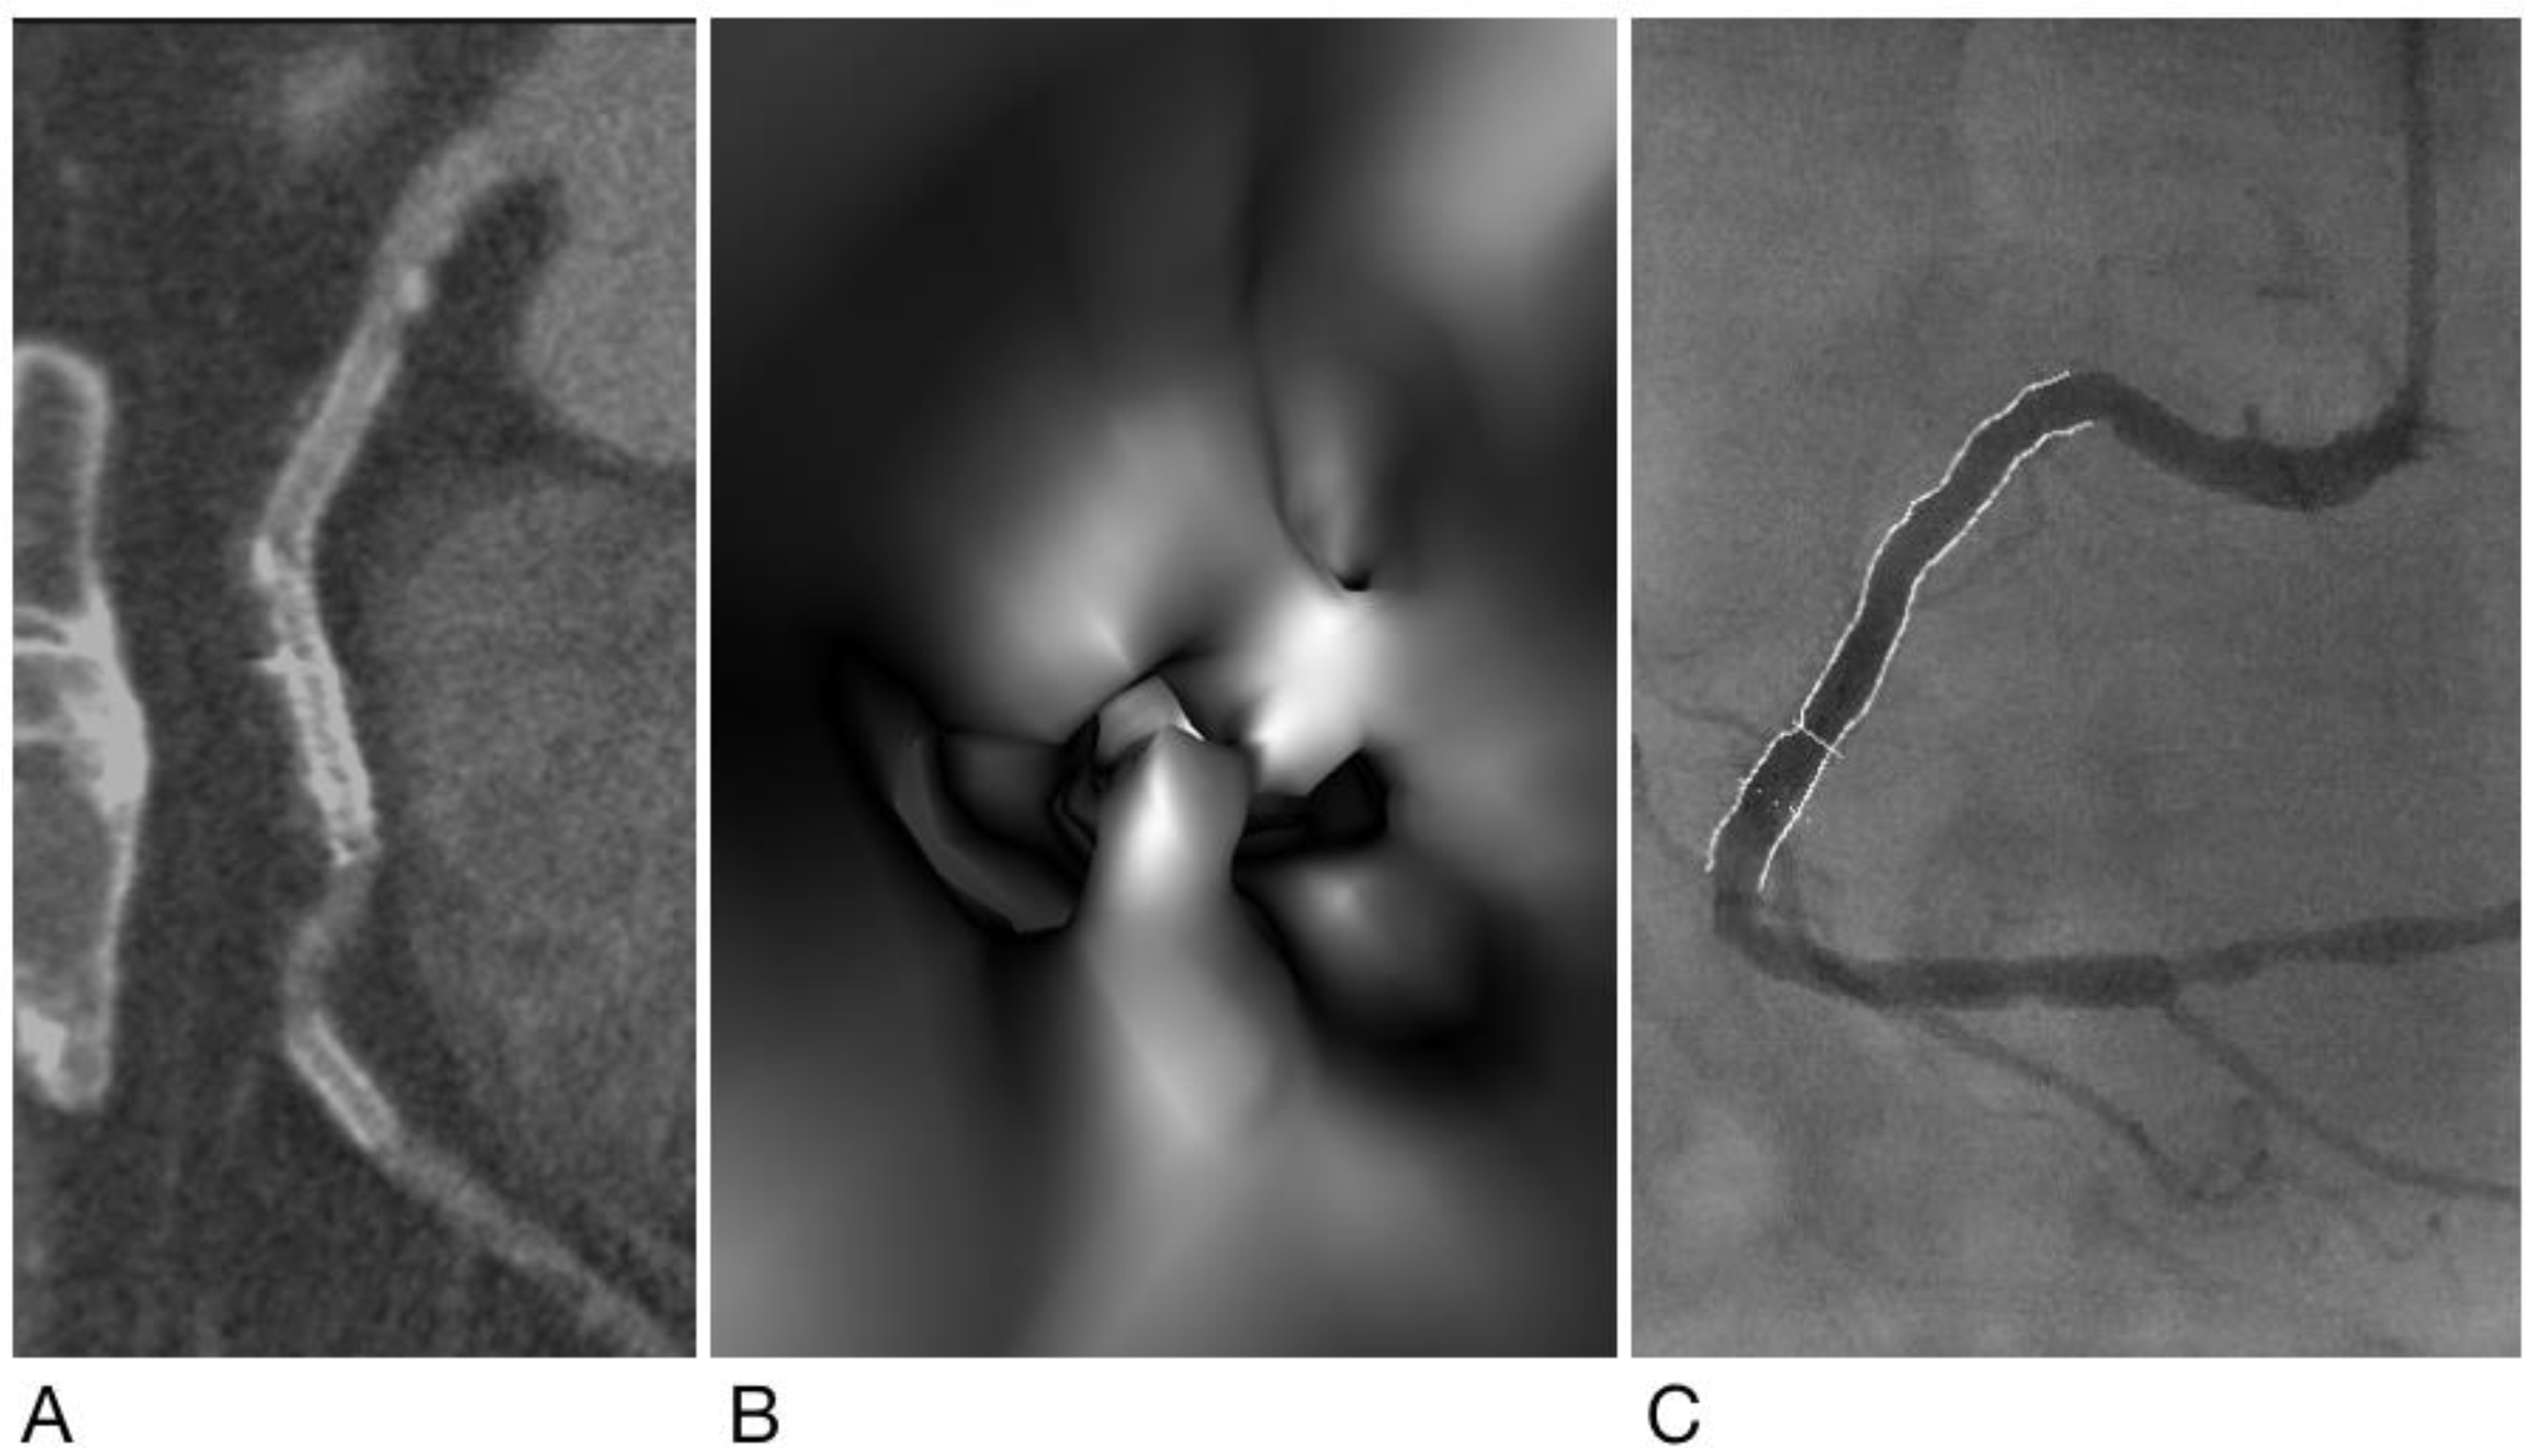

2.4. Generation of Virtual Intravascular Endoscopy Images

- Sun, Z.; Dimpudus, F.J.; Nugroho, J.; Adipranoto, J.D. CT virtual intravascular endoscopy assessment of coronary artery plaques: A preliminary study. Eur. J. Radiol. 2010, 75, e112–e119. [Google Scholar] [CrossRef] [PubMed]

- Xu, L.; Sun, Z. Virtual intravascular endoscopy visualization of calcified coronary plaques: A novel approach of identifying plaque features for more accurate assessment of coronary lumen stenosis. Medicine 2015, 94, e805. [Google Scholar] [CrossRef] [PubMed]

- Sun, Z.; Xu, L. CT virtual intravascular endoscopy in the visualization of coronary plaques: A pictorial essay. Curr. Med. Imaging Rev. 2017, 13, 154–161. [Google Scholar] [CrossRef][Green Version]